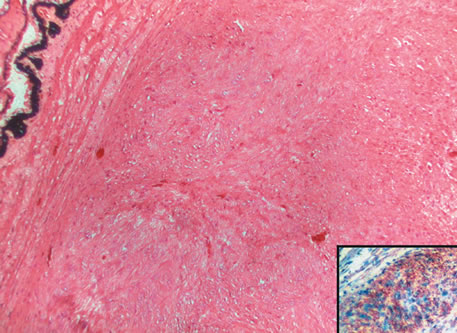

Inflammatory conditions may also lead to iris nodules. Patients suffering from fungal endophthalmitis may demonstrate an irregular yellow-white mass on the iris. Histologically, these appear as necrotizing granulomas containing mycotic agents (Fig. 2). In juvenile xanthogranuloma, a yellowish-gray iris lesion may be associated with spontaneous hyphema, and histopathologically the nodules demonstrate diffuse histiocytic infiltrate (Fig. 3). Multinucleated giant cells displaying peripheral foamy cytoplasm are also noted; these cells are known as Touton giant cells.29 The giant cells and the histiocytes contain lipid that can be demonstrated by oil red O stain.

Fig. 3. Juvenile xanthogranuloma. The iris is infiltrated by histiocytes, which form nodular aggregates on the anterior surface of the iris. (Hemotoxylin-eosin ×25.) Inset (×200) shows oil red O-positive histiocytes.